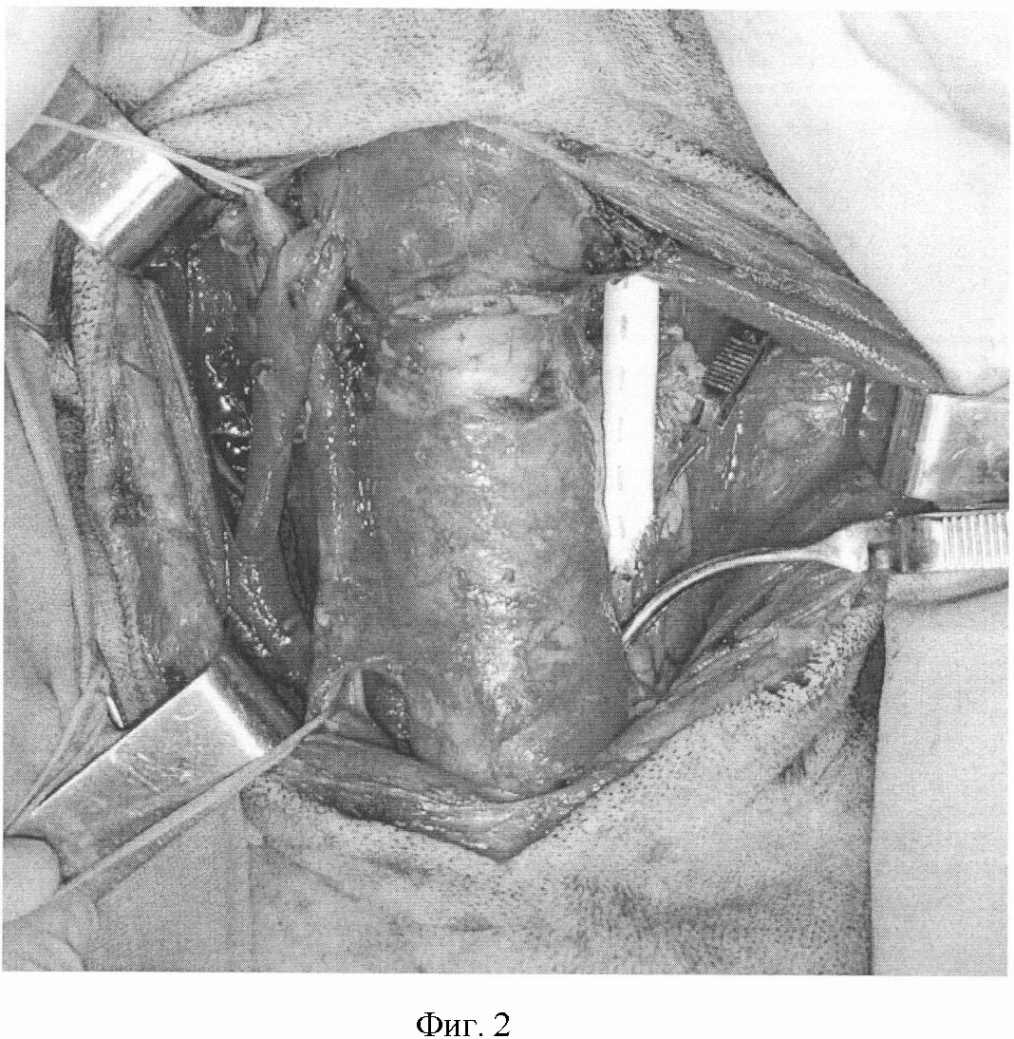

Фиг.2. Иссечен и протезирован участок левой сонной артерии, пережат участок правой сонной артерии.